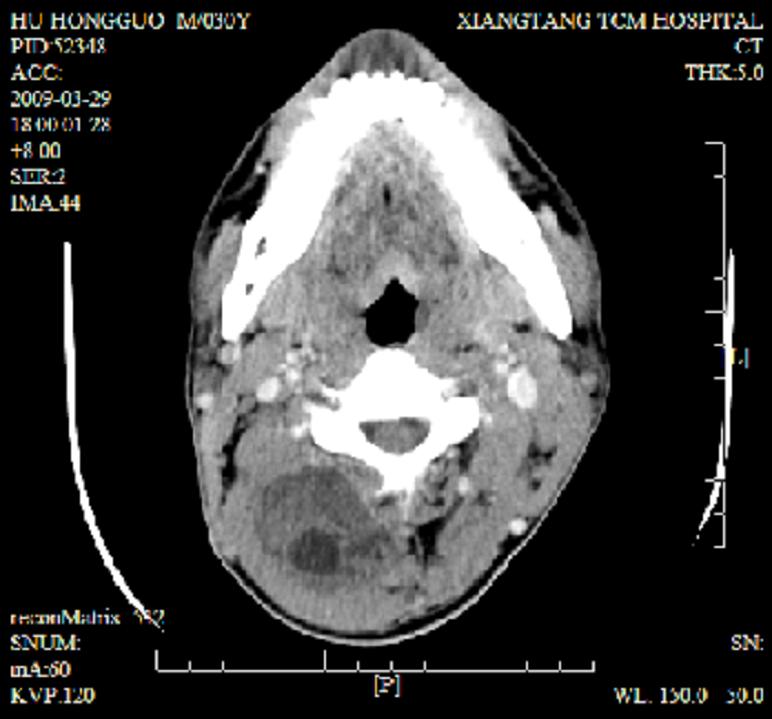

标题: CT19102:颈部肿块

男30y发现肿块3年

多处囊实性肿块,形态欠规则有一定形态,内见点状钙化,以囊变为主,增强后轻度强化,首先考虑神经源性肿瘤如鞘瘤,不除外脉管源性肿瘤如淋巴管瘤(见缝钻及囊性区域太多,如果合并感染完全可以这个影像表现),和海绵状血管瘤,但是血管瘤不太支持因为强化特征和病灶形态不典型.

右侧椎前间隙后部肌间、皮下囊性为主病变,可见分隔和点状钙化,分隔和壁呈轻度环形强化,大部分无强化。形态不规则,有钻缝特点。考虑1 淋巴管瘤合并感染2 血管平滑肌脂肪瘤3 表皮样囊肿4 不除外海绵状血管瘤。

病灶沿皮下及肌间隙爬行,病灶内有钙化灶,病灶有强化。病史3年,病人应该没什么症状。考虑纤维血管瘤可能性大。